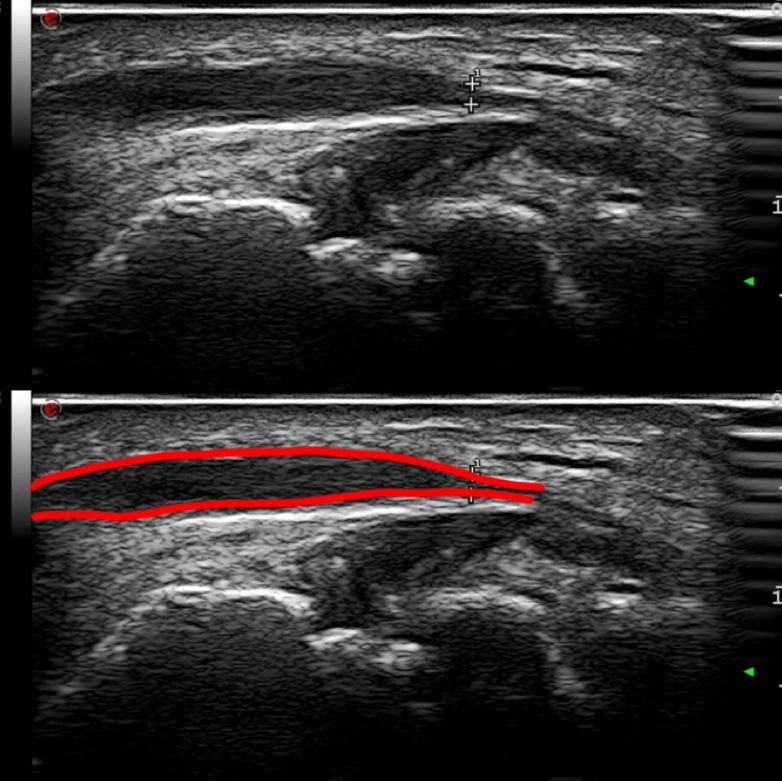

图2

右侧尺神经受压,内径明显变细

图3

尺神经近端增宽,回声减低,神经束显 示模糊。